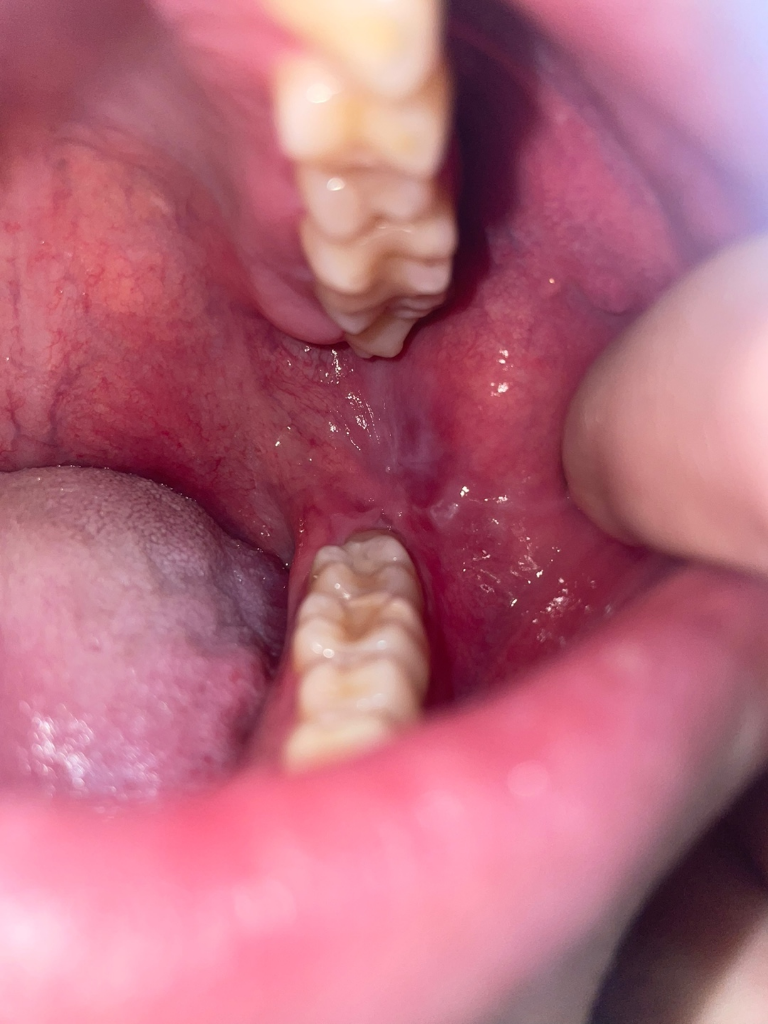

양쪽 어금니 쪽 볼에 혹?처럼 뭐가 생겼어요 깨문기억은 없는데 혹시 구강암이런것과 관련있나요?

한 3일전쯤까진 없었는데 그쯤 양쪽 어금니 쪽에 볼에 혹? 염증? 같은 그런게 생겼어요

그리고 사진에 보면 어금니 뒤쪽 흰색부분이 있는데 이건 왜 그럴까요 이건 언제부터 생긴건지는 모르겠습니다. 잘 안보이실까 하여 표시안한 원본사진도 첨부합니다

해당부위는 볼의 연조직이 치아 사이에 밀려 들어가면서 생기는 증상으로 보입니다.

구강암이 아니고 볼이 치아에 씹혀서 생긴겁니다. 문제가 잇는건 아니니 너무 걱정하지마세요.

사진상으로는 씹어서 생긴 외상성 궤양이 맞습니다

특별히 치아에 보철치료나 충치치료를 하고 생긴 변화가 아니기 때문에 치과적으로 처치를 해줄 건 없고 외상성 궤양도 시간이 지나면 자연스럽게 회복됩니다. 좀 더 빠른 회복을 위해서는 구강 내에 적용하는 연고를 바르셔도 좋습니다.